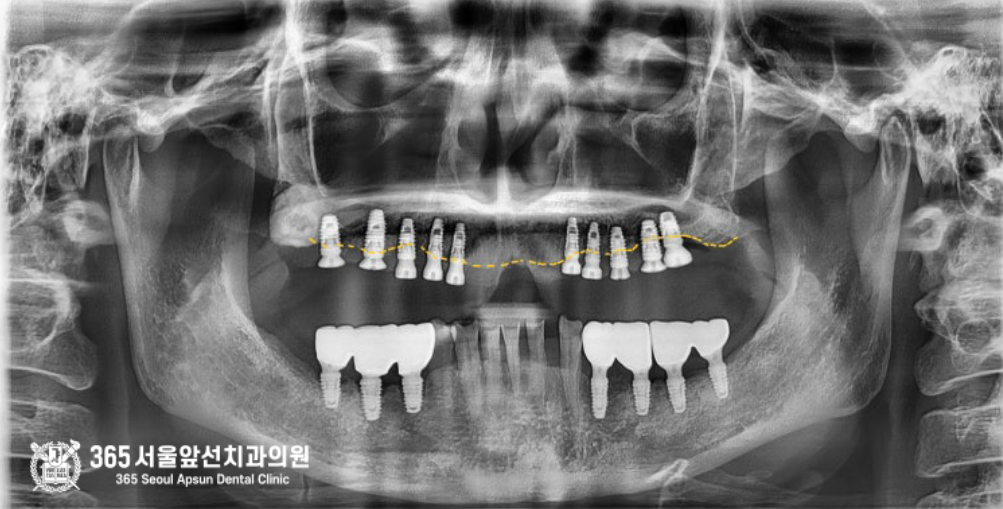

촬영일시 : 2024.06.12 문제가 있던 기존의 임플란트를 모두 제거했습니다.

촬영일시: 2024.06.12 기존 임플란트를 모두 제거했고, 제거와 동시에 한번에 좌우측 상악동 뼈이식까지 진행하며 새로운 임플란트를 식립해드렸습니다.